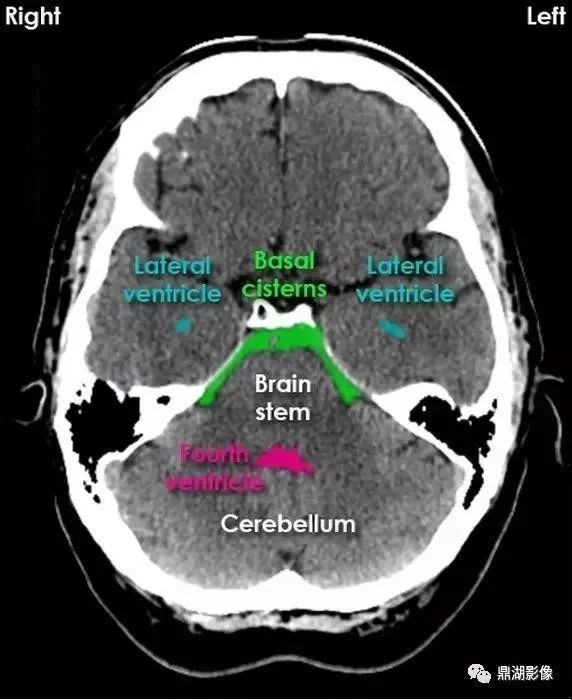

大脑ct结构图

10张图搞定正常头颅ct断层解剖

一套非常牛的头颅ct解剖图谱

详细标注版——颅脑ct正常解剖图谱_中央_小脑_纤维

超赞的高清颅脑ct解剖彩色图谱